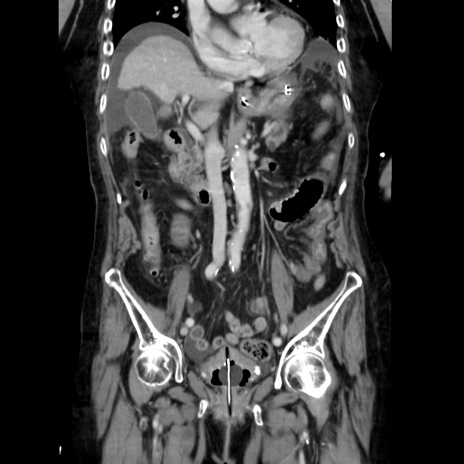

症例40(冠状断像)

【症例】90歳代女性

【主訴】腹痛・嘔吐

【現病歴】 食欲低下、嘔吐があり昨日他院受診。肺炎と診断され入院となる。入院後より腹部全体に圧痛あり。胃管留置され経過みていたが、症状持続するため、

当院転院となる。

【既往歴】胸椎圧迫骨折、胆石症

【身体所見】腹部:中央に激痛あり、圧痛あり、反跳痛不明

【データ】WBC 17100、CRP 18.82

冠状断像